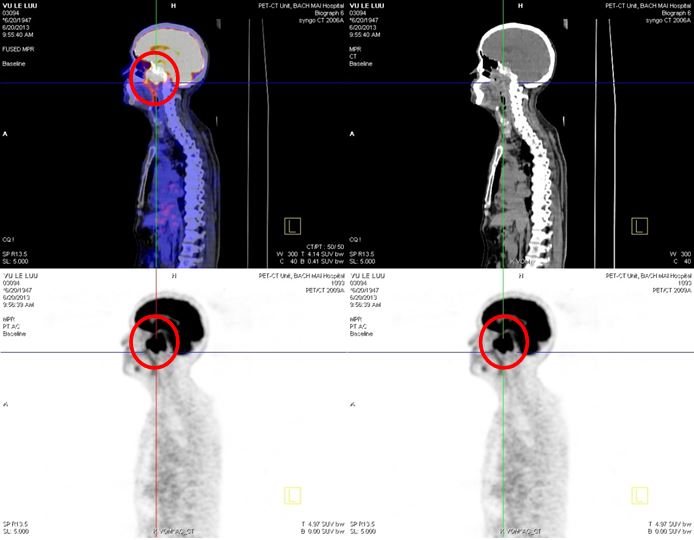

- Chụp PET/CT với 18F-FDG

Hình 3. Hình ảnh PET/CT trước điều trị: khối u vòm họng kích thước (4,5 x 6,2 x 4,3)cm, xâm lấn nền sọ tăng hấp thu FDG max SUV: 14,8 (mũi tên hoặc vòng tròn), không thấy tăng hấp thu FDG tại các vị trí khác của cơ thể.